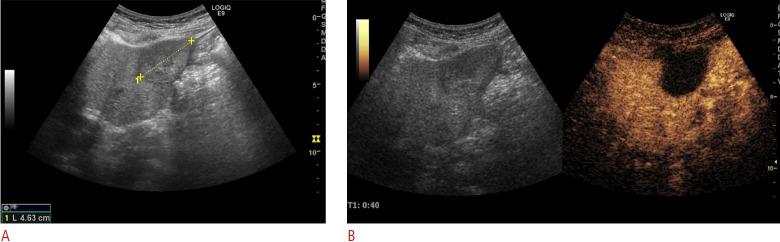

Ablation is a valuable treatment alternative to surgery for colorectal liver metastases. This study reports the long-term clinical outcomes in patients treated with ablation for colorectal liver metastases with or without extrahepatic metastases.

Patients with colorectal liver metastases treated with ultrasound-guided ablation at Herlev Hospital, Denmark were included in this retrospective study.

对于结直肠癌肝转移患者,消融术是一种有价值的手术替代治疗方法。本研究报告了接受消融术治疗的有或无肝外转移的结直肠癌肝转移患者的长期临床结局。

本回顾性研究纳入了在丹麦赫勒夫医院接受超声引导下消融术治疗的结直肠癌肝转移患者。